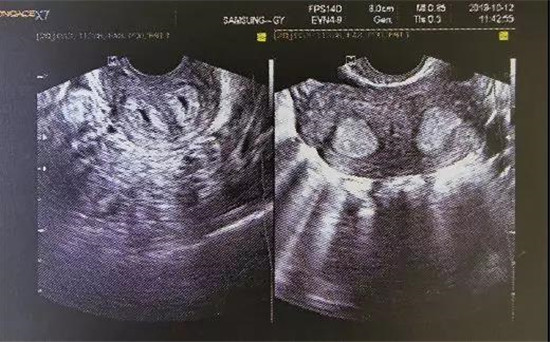

小杨是上个月雅安恒博医院业务副院长-妇产科冷艳主任医师收治的一位纵隔子宫患者,今年21岁,未婚有同居男友。“小杨的情况属于子宫完全纵隔、阴道完全纵隔、双宫颈,右侧卵巢还有5cm左右大小畸胎瘤。”冷艳说。

小杨的情况就属于是第一种,并且还是双宫颈、阴道完全纵隔。纵隔子宫通常无症状,但影响大。纵隔子宫女性与普通女性没有什么区别,通常只有在超声检查时,才会发现端倪,对女性最大的影响在于“生宝宝”这道关卡。